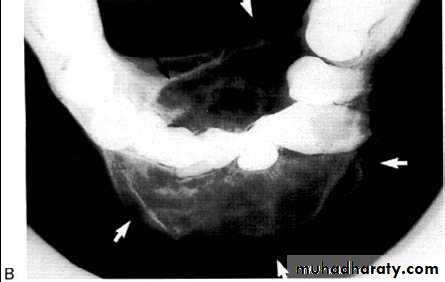

Multilocular appearance, expansion (arrowed) and considerable displacement of the adjacent teeth.

Buccal and lingual expansion (arrowed) and the undulating cortical border.

• Aneurysmal Bone Cyst

•Large multilocular aneurysmal bone cyst

in the ramus with marked expansion and

the displacement of/8.

It is non-neoplastic ,exaggerated,localized, proliferative lesion of vascular tissue, containing giant cells.

It’s a variation of the central giant cell granuloma , can be diagnosed only by histological examination